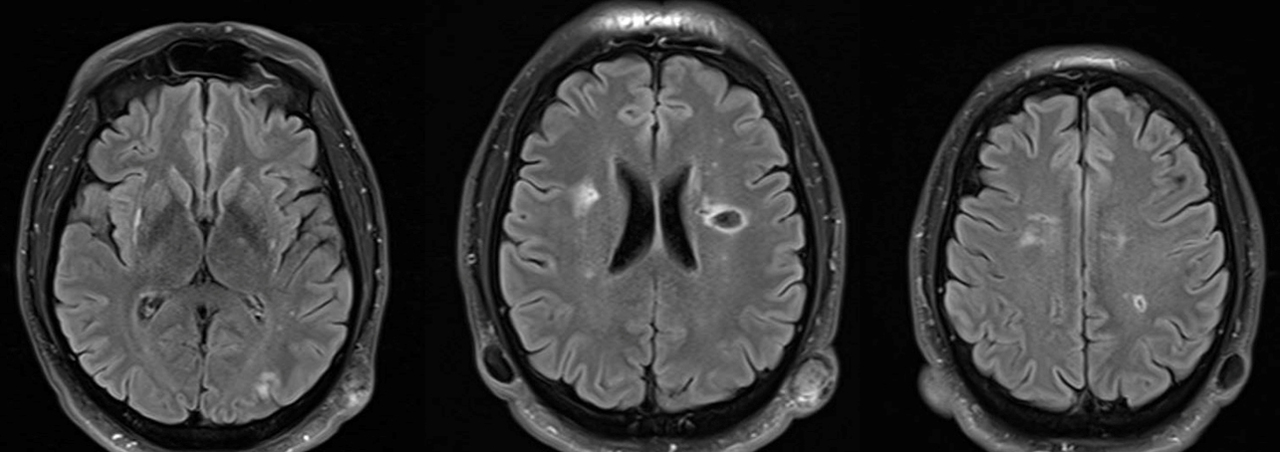

Le type d’hémianopsie est très important car il permet de localiser une atteinte neurologique, en connaissant le trajet des voies optiques.

Figure d’après le Collège des enseignants de neurologie (CEN). Altération aiguë de la vision.

Cette question supposait d’avoir bien en tête le schéma des voies optiques, et d’avoir des repères sur les principaux territoires vasculaires cérébraux et l’atteinte clinique associée. Il bien mentionné par le CEN que l’hémianopsie latérale homonyme gauche peut se voir dans un AVC sylvien superficiel droit.

Tableau d’après le Collège des enseignants de neurologie. Altération aiguë de la vision.